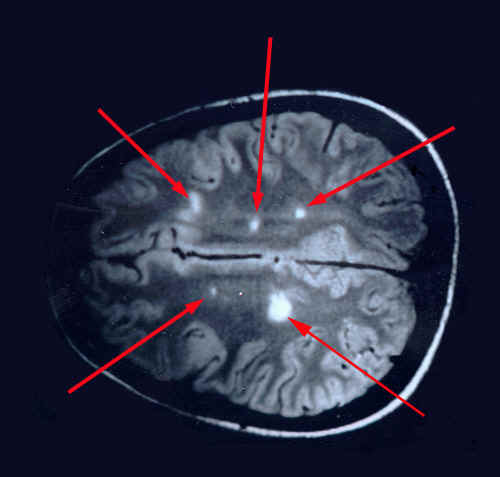

Рассеянный склероз

Медицинская статья в раздел "Справочник заболеваний"

medihost.ru/glossary/diseases/rasseyannyy_skleroz_...